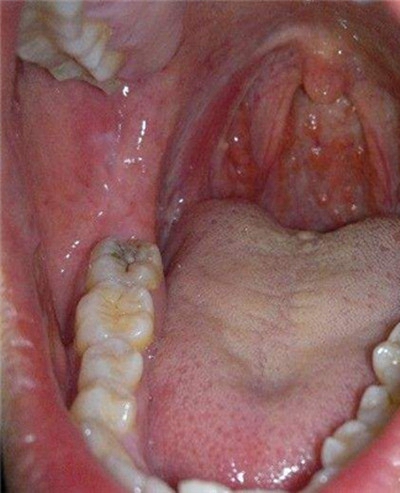

慢性咽喉炎圖片

喉部淋巴濾泡增生 (45)